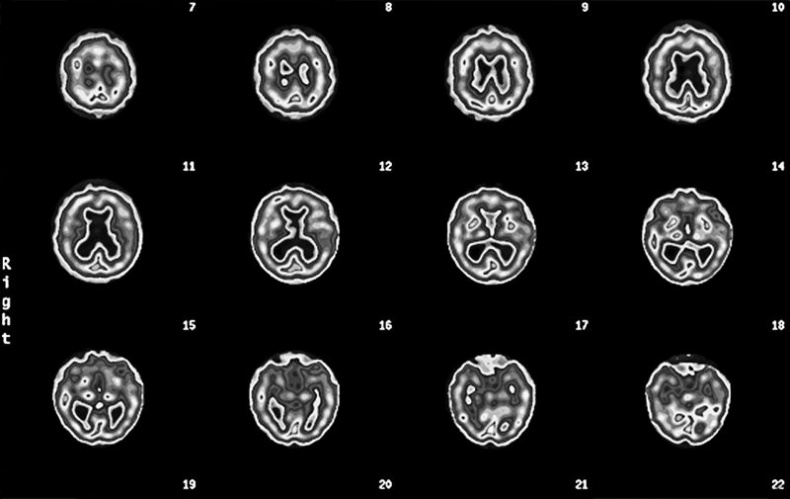

Больше узнать о состоянии здоровья своего мозга и риске развития болезни Альцгеймера поможет томограмма ОЭКТ. Когда мне исполнилось 50, мой лечащий врач назначил плановую колоноскопию. «А почему вы не хотите проверить мой мозг, – поинтересовался я, – разве другой конец туловища не столь важен?» Как узнать, что происходит в мозге, если не обследовать его? Я верю, что томограф в ближайшем будущем станет таким же привычным инструментом диагностики, как маммограф или колоноскоп. Он принесет особую пользу людям из группы риска и тем, у кого уже появились «ранние» симптомы. Поскольку большинство врачей еще не привыкли к томографии, многие пациенты узнают о своих проблемах «в голове», когда уже слишком поздно. А ведь на раннем этапе эти заболевания можно корректировать. Вот пример. Эд Эду семьдесят два, его дочь Кэндис привезла его к нам на прием из Ванкувера, Британская Колумбия. Кэндис была встревожена забывчивостью отца. Его настроение было хуже обычного, а суждения не столь хороши, как прежде. Некоторые финансовые счета он оплачивал дважды, а о других мог забыть. Когда она отвела его к местному невропатологу, тот диагностировал болезнь Альцгеймера, не сделав томограмму его мозга. Кэндис прочитала мою книгу «Измените свой мозг – и жизнь изменится» и расстроилась, что врач не сделал томограмму. Скан мозга Эда (горизонтальные срезы мозга показаны по направлению сверху вниз) ![]() См. срезы 15 и 16 и увидите «лобстера» Скан нормального мозга ![]() Полная, равномерная, симметричная активность Скан ОЭКТ мозга Эда ![]() Нетипичная структура для болезни Альцгеймера, мы видим увеличенные желудочки («дыра» в середине) и маленький мозжечок (в основании) Врач ответил, что уверен в своем диагнозе и не нуждается в подтверждении. Меня такое отношение всегда неприятно удивляет. Недовольная поведением врача, Кэндис привезла Эда к нам. На скане мозга Эда было видно, что желудочки мозга (заполненные жидкостью полости) увеличены. Такой рисунок на томограмме я называю лобстером, потому что он похож на перевернутого омара. Еще у Эда был слишком маленький мозжечок. Томограмма Эда определенно не походила на типичную картину поражения, которую мы наблюдаем при болезни Альцгеймера (низкая активность височных и теменных долей). Зато картина, как у Эда, часто обнаруживается при заболевании под названием «гидроцефалия с нормальным давлением». При ней блокируется нормальный отток жидкости из желудочков мозга и количество жидкости в них постепенно возрастает. Одновременно могут проявляться такие симптомы, как недержание мочи и нарушение походки, хотя и не обязательно. Поскольку этих симптомов у Эда не было, его невролог даже не подумал о другом диагнозе. А состояние Эда продолжало ухудшаться. Увидев скан, я сразу назначил консультацию с нейрохирургом. Тот согласился с моим диагнозом и провел шунтирование мозга Эда. Память восстановилась в течение 3 недель. Как можно помочь, если не посмотреть на пострадавший орган? ШАГ 3. Сосредоточьтесь на уменьшении специфических факторов риска Итак, вы представляете, какие факторы риска существуют. Что с ними делать? Вот список факторов и действий. • Фактор риска: Член семьи с болезнью Альцгеймера или схожим нарушением, либо у вас есть ген APO e4. • Действие: Проведите ранний скрининг и со всей серьезностью как можно раньше займитесь профилактикой. Реализуйте все описанные в этой книге стратегии прямо сейчас. • Фактор риска: Единичная черепно-мозговая травма или несколько черепно-мозговых травм. • Действие: Предотвращайте повторные черепно-мозговые травмы, как можно скорее реализуйте стратегии профилактики. • Фактор риска: Алкоголизм, наркотическая зависимость или курение в прошлом либо настоящем. • Действие: Остановите лечение и ищите скрытые причины, как можно раньше начинайте стратегии профилактики. • Фактор риска: Тяжелая депрессия или СДВ(Г), диагностированные врачом в прошлом или настоящем. • Действие: Лечитесь, занимайтесь профилактикой. • Фактор риска: Инсульт, болезнь сердца, высокий уровень холестерина, артериальная гипертензия, диабет, история лечения рака, эпилептические припадки в прошлом или настоящем. • Действие: Лечение и стратегии профилактики. • Фактор риска: Ограниченная физическая нагрузка (меньше двух получасовых тренировок в неделю). • Действие: тренируйтесь три раза в неделю или больше. • Фактор риска: Образование ниже среднего школьного или работа, не требующая периодического освоения новой информации. • Действие: Учитесь всю жизнь, непрерывно. • Фактор риска: Сонное апноэ. • Действие: Пройдите осмотр и займитесь лечением апноэ. • Фактор риска: Дефицит эстрогена или тестостерона. • Действие: Подумайте о гормонозаместительной терапии. Думаю, вы поняли принцип. Устраните факторы риска, которые поддаются уменьшению, и работайте над долгосрочным здоровьем мозга. ШАГ 4. Поддерживайте активность тела и мозга В следующих главах вы увидите, что физические и умственные тренировки – это лучший способ сохранить молодость мозга. Тренировка ума помогает мозгу укрепить имеющиеся синаптические связи и создавать новые. Больше об интеллектуальных тренировках вы узнаете в главе 5. Физические упражнения повышают приток крови к мозгу, улучшают его обеспечение кислородом и помогают защитить мозг от вредных молекул, таких как свободные радикалы. Подробнее о физических упражнениях будет рассказано в главе 3. ШАГ 5. Принимайте пищевые добавки для поддержания здоровой функции мозга О пищевых добавках накоплено много информации, а также дезинформации. Отделить истину от заблуждений очень важно, потому что некоторые добавки действительно работают. Каждый день принимайте поливитамины и рыбий жир. Проверьте свои показатели витамина D и при необходимости оптимизируйте их. Вот еще несколько доказавших свою эффективность добавок. • Рыбий жир и куркумин для уменьшения воспалений. • N-ацетилцистеин и альфа-липоевая кислота – чтобы повысить сопротивляемость тела свободным радикалам и окислительному стрессу. |